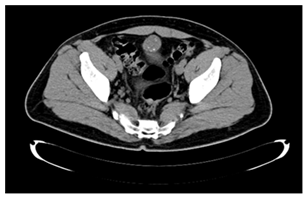

A 41-year-old male patient, who went to the Urology service of the Medical Center Lic. Adolfo Ruiz Cortines (IMSS) by macroscopic hematuria, no clots formation, associated with pain in the hypogastrium. He reported weight loss of 10 kg in three months. Physical examination was observed the abdomen with discrete volume increase in the hypogastrium and palpation a tumor of Approximately 5 cm, depending on the scar umbilical, mobile, not painful or fixed in the deep planes, slightly indurated. Laboratory studies reported cytometry hematics within the normal parameters; blood chemistry with glycemia of 164 mg/dL, urea of ​​40 mg/dL and creatinine 1.1 mg/dL. The general examination of urine with glycosuria, proteinuria, hemoglobin (+) and numerous erythrocytes. The ultrasound abdominal bladder showed a lobed image, of heterogeneous content adjacent to the upper wall. Abdominal-pelvic tomography (Figure 1) and (Figure 2) reported: free retroperitoneum lymphadenopathy, morphology of large vessels with normal diameter and path; in the cavity pelvic urinary bladder was observed with thickening from the wall and in the middle line the wall anterior with irregular, heterogeneous image, which was enhanced with the contrast medium, with towards the abdominal cavity and wall, 38 x 27 mm, with multiple calcifications Punctiform peripherals. (Figure 3) evidenced a tumor in the bladder dome of solid aspect, with zones of brown color, approximate diameter of 3 cm and irregular edges. The treatment consisted of Transurethral resection of the bladder, with results satisfactory.

Figure 1 Tomography (axial) showing multiple punctate peripheral calcifications.